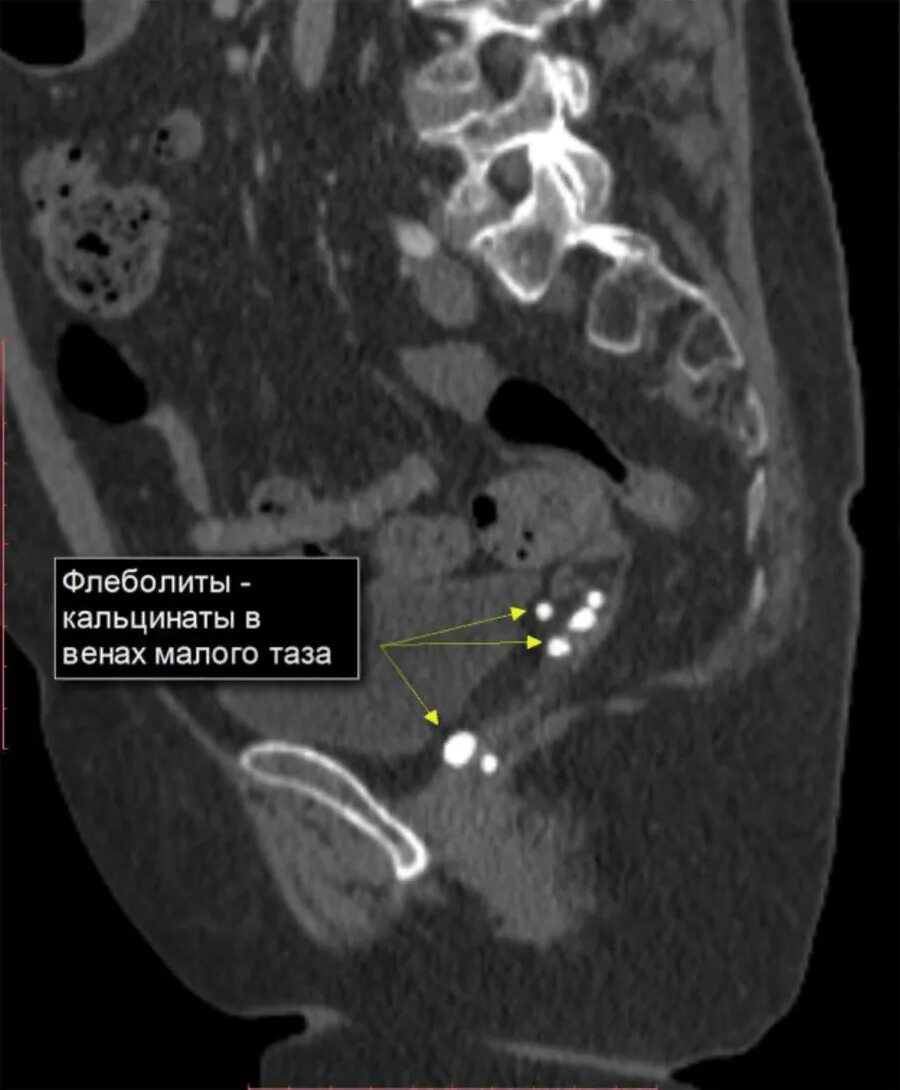

Инволютивные изменения яичников